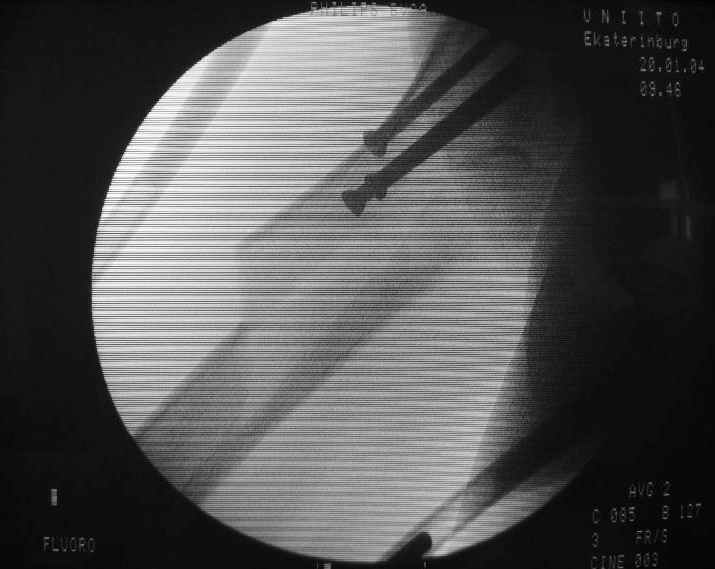

Alexander Chelnokov 21 Январь 2004, 09:05

Вчера оперировали - винты удалены через 1 прокол. Затем выполнили закрытый интрамедуллярный остеосинтез без расверливания бесканальным гвоздем 13 мм (реконструкционного для нее не нашлось). Гвоздь заперт статически - в проксимальный отломок 3 винта 6 мм, в дистальный - 1.

Учитывая варус сросшейся шейки, постарался вальгизировать проксимальный отломок, насколько гвоздь позволил. Результат в приложении. Картина перелома видна лучше, чем на начальных снимках.

Интересно, что линия перелома не выходила на отверстия от винтов, а была кзади. Комментарии?

The screws were removed through a stab wound. Then a closed insertion of an unreamed solid nail 13 mm was performed and the nail statically locked - 3 screws 6 mm in the proximal fragment and 1 in the distal.

Considering varus of the healed neck i tried to get some valgus to the proximal fragment as the nail allowed. The result attached. The fracture pattern can be seen better than in the initial films.

Any comments?